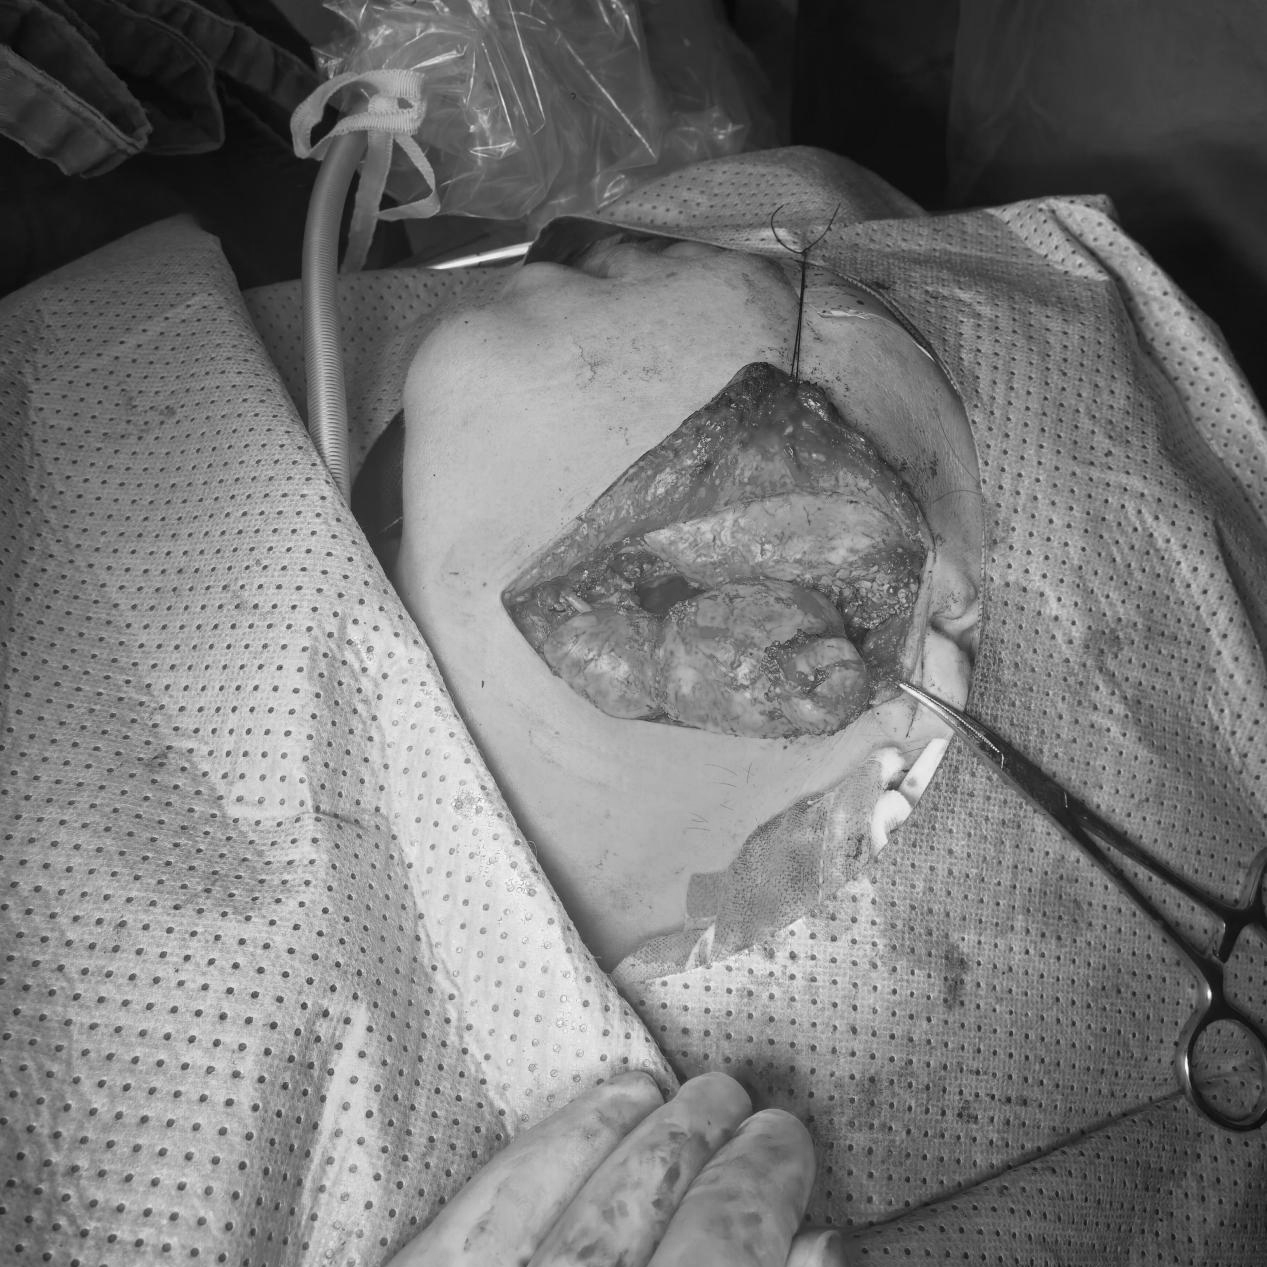

近日, 头颈外科团队成功为一位咽旁间隙巨大肿瘤患者施行了肿瘤切除术。肿瘤体积大,范围达左右46mm✖前后35mm✖上下75mm,且位于解剖结构复杂、位置深的咽旁间隙,手术难度高。

患者为57岁女性,因“头痛3年”前来我院门诊就诊,CT检查发现左侧咽旁间隙肿瘤,咽旁间隙是头颈部一个深在的潜在腔隙,结构复杂,内含重要的血管、神经。该患者的肿瘤在此处生长,体积巨大,对周围组织造成了明显的挤压和推移。如此大的肿瘤完整切除,不仅要求主刀医生具备精湛的显微外科技术和扎实的解剖知识,更需要整个团队默契配合,对术前评估、手术入路选择、术中风险控制和术后管理都提出了极致挑战。

图片 1.png